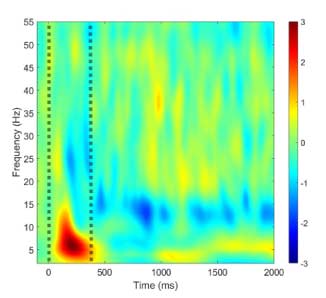

Disease mechanisms of Tourette syndrome

Tourette syndrome (TS) is defined by the presence of tics, but abundant evidence shows the disorder is multifaceted. Sensory and psychiatric symptoms occur in 90% of patients, and these symptoms impact quality of life to a greater extent than tics. Our research seeks to understand the interrelationship between motor, sensory, and psychiatric manifestations of TS, with the ultimate goal of identifying novel treatment targets for the disorder. Our research program involves parallel clinical and translational efforts. Clinically, we conduct cohort studies in children and adults with TS to quantify changes in tic severity, sensory perception, and mental health over time. Translationally, we use electroencephalography (EEG) to identify physiologic correlates of TS symptoms, thereby deepening insights into disease mechanisms and paving the way for clinically meaningful biomarkers.

Neurophysiology of consciousness and cognition

Dr. Williams Roberson’s team studies the brain activity patterns underlying consciousness and cognitive functions such as language production, perception and memory, and seeks to use these patterns to optimize the care of patients with central nervous system disorders such as delirium, dementia, epilepsy, and stroke. We use computational and quantitative analysis techniques to investigate the neurophysiological basis of cognitive functions in health and in neurologically impaired states. We are currently conducting an observational study developing quantitative EEG-based biomarkers of ICU delirium, post-ICU cognitive impairment and post-ICU psychological distress. We will use these biomarkers to identify patients most at risk for symptoms of post-intensive care syndrome (PICS), and subsequently to develop and validate targeted neuromodulatory interventions to improve cognitive and psychological outcomes in survivors of critical illness.